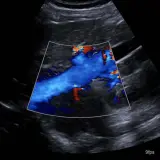

Ultrasound

75 cases Covering OB/GYN, GI/GU, and more